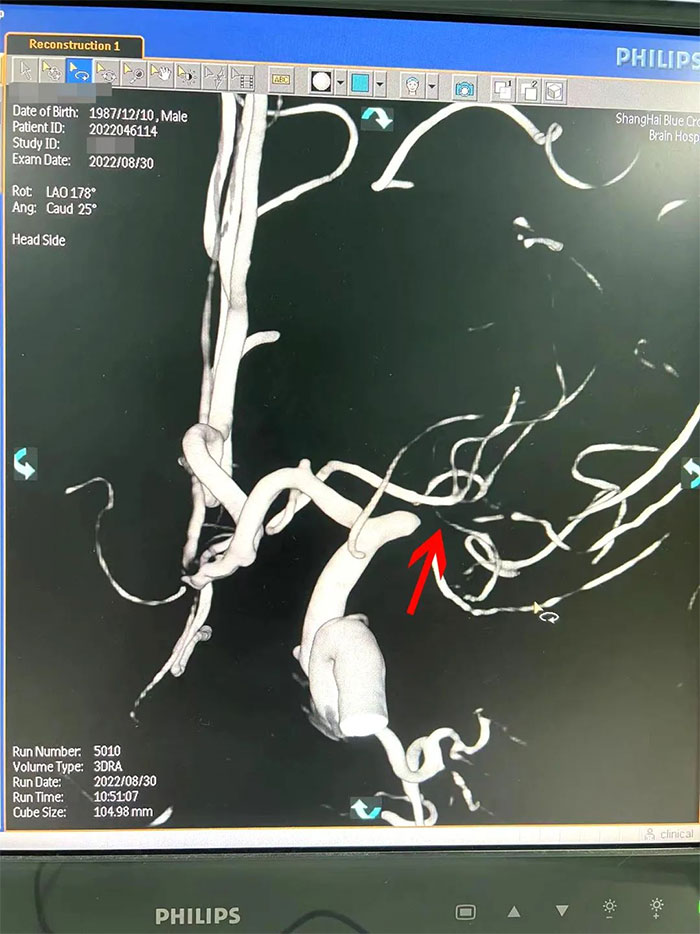

在检查中发现,周先生右侧大脑中动脉M1段闭塞,可见烟雾状异常血管网生成;左侧大脑中动脉M1段重度狭窄(约70%)。符合烟雾病的典型影像学特征。

▲右侧大脑中动脉M1段闭塞,左侧重度狭窄

烟雾病又名Moyamoya病,脑底异常血管网,是一组以Willis环双侧主要分支血管(颈内动脉虹吸段及大脑前、中动脉,有时也包括大脑后动脉)起始部慢性进行性狭窄或闭塞,继发出现侧支异常的小血管网为特点的脑血管病。因脑血管造影时,呈现许多密集成堆的小血管影,似吸烟时吐出的烟雾而得名。